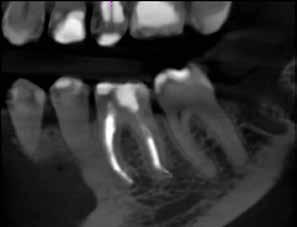

Mind a periapicalis röntgenfelvétel, mind a CBCT-felvétel igazolta, hogy a fragmentum mélyen a gyökércsatorna görbülete mögött, az apikális harmadban helyezkedik el a mesiobuccalis csatornában, valahol a mesiolingualis csatornával történő egyesülés után. Ezenfelül mind a mesialis, mind a distalis gyökércsúcs körül periapicalis gyulladás jelei voltak megfigyelhetőek (1–3. ábra). A betört eszköz nagyjából 5 mm-es hosszúsággal rendelkezett. A mesiolingualis csatornán keresztül a betört fragmentum mellett történő további gyökércsatorna-megmunkálást kockázatosnak ítéltük, mivel nagy esélyt láttunk rá, hogy így a másik eszköz is eltörik, amely pedig a gyökértömés elkészítését nehezítette volna. Azonban a SWEEPS technológiának és a biokerámia sealereknek köszönhetően más megoldási lehetőségek is nyitva álltak előttünk.

ábra: Kiindulási röntgen. A felvételen jól látható a betört eszköz és a periapikális lézió.

2. ábra: Kiindulási CBCT-felvétel. A betört eszköz mélyen a gyökércsatorna görbülete mögött található.

3. ábra: A betört eszköz vége jóval a mesiobuccalis és mesiolinguális csatorna egyesülésének pontja alatt helyezkedik el.